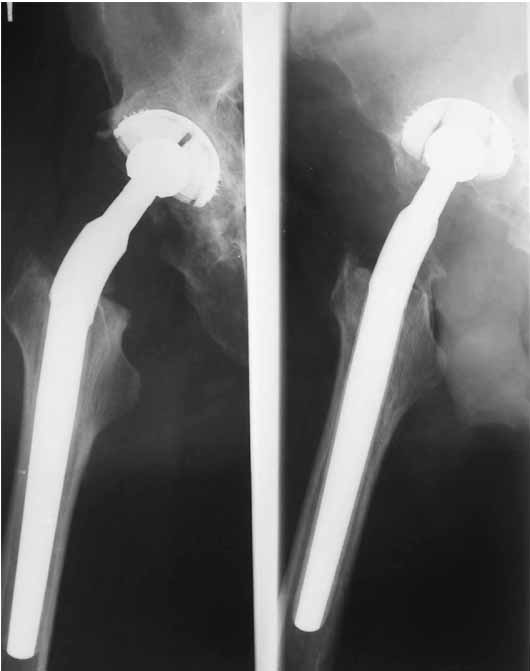

Во вложении - рентгенограммы после вывиха и после вправления.

Идея очень простая, в случае, если удасться прожить без вывиха 2.5-3 месяца, вероятность его возникновения в будущем значительно уменьшится. Оптимальный вариант - повторная иммобилизация на срок 6 недель с нагрузкой на ногу (как бы я ни не любил гипс, но этот путь проверенный и может дать результат). Если это невозможно, то исключительно осторожная реабилитация под строгим контролем без резких движений (спать в положении на спине с отведением и подушкой под коленкой и т.д.). Ходьба сама по себе не опасна, опасен переход от положения "лежа" в положение "полусидя" и "стоя" и наоборот.